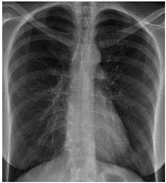

Furthermore, some of the examples of the COVID-19 positive and the healthy patients from the dataset are included in Table 5. The clinical data represent the attributes sequence, i.e., gender, age, body temperature, pulse rate, respiratory rate, blood pressure systolic, blood pressure diastolic, shortness of breath, cough, other symptoms, diabetes mellitus, hypertension, cardiac disease, dyslipoproteinemia, chronic kidney disease, and other chronic diseases.

Table 5.

Sample CXR and clinical data for the COVID-19 positive and healthy cases.